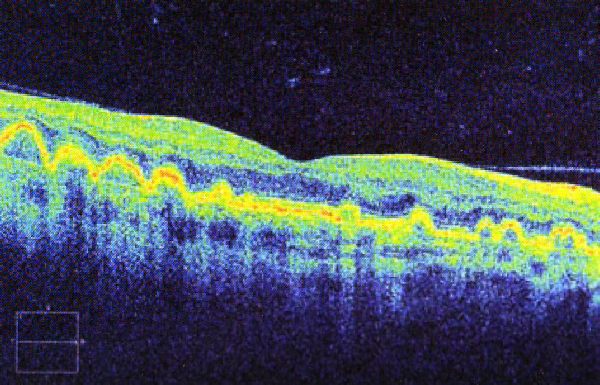

Optical Coherence Tomography uses low intensity infra-red light to give a 3D image of the back of the eye.  It shows not only the surface but also the depth of the structures.  It is similar to using ultrasound and creates an image not unlike an MRI or CT scan.

A 3D section of the layers ofthe retina and vitreous jellyA 3D section of the layers of the retina and vitreous jellyAge-related Macular Degeneration Dry FormAge-related Macular Degeneration Dry FormAge-related Macular Degeneration Wet FormAge-related Macular Degeneration Wet FormThe vitreous (jelly) pulling on the retinaThe vitreous (jelly) pulling on the retinaImage of Retina (back of the eye)Image of Retina (back of the eye)